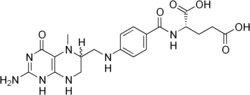

![]() | |

| 5-methyltetrahydrofolate is decreased in concentration in the human brain | |

Cerebral folate deficiency is a condition in which concentrations of 5-methyltetrahydrofolate are low in the brain as measured in the cerebral spinal fluid despite being normal in the blood.[3] Symptoms typically appear at about 5 to 24 months of age.[3][2] Without treatment there may be poor muscle tone, trouble with coordination, trouble talking, and seizures.[3]